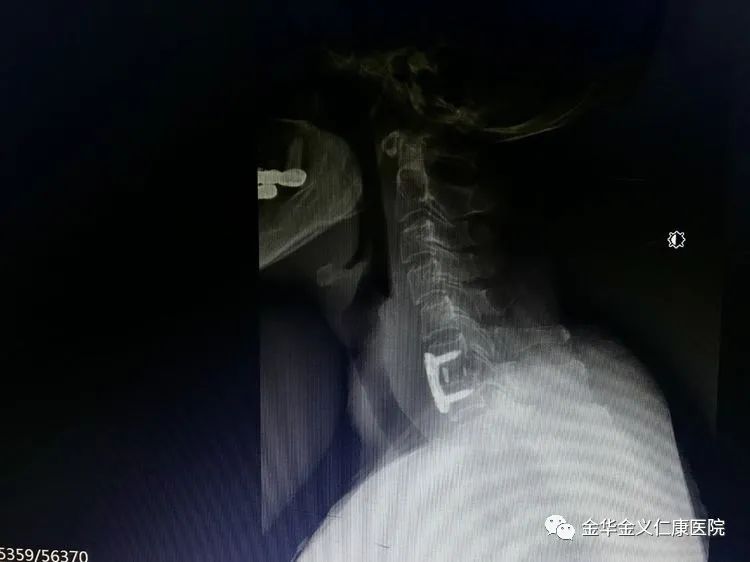

术后的X光片